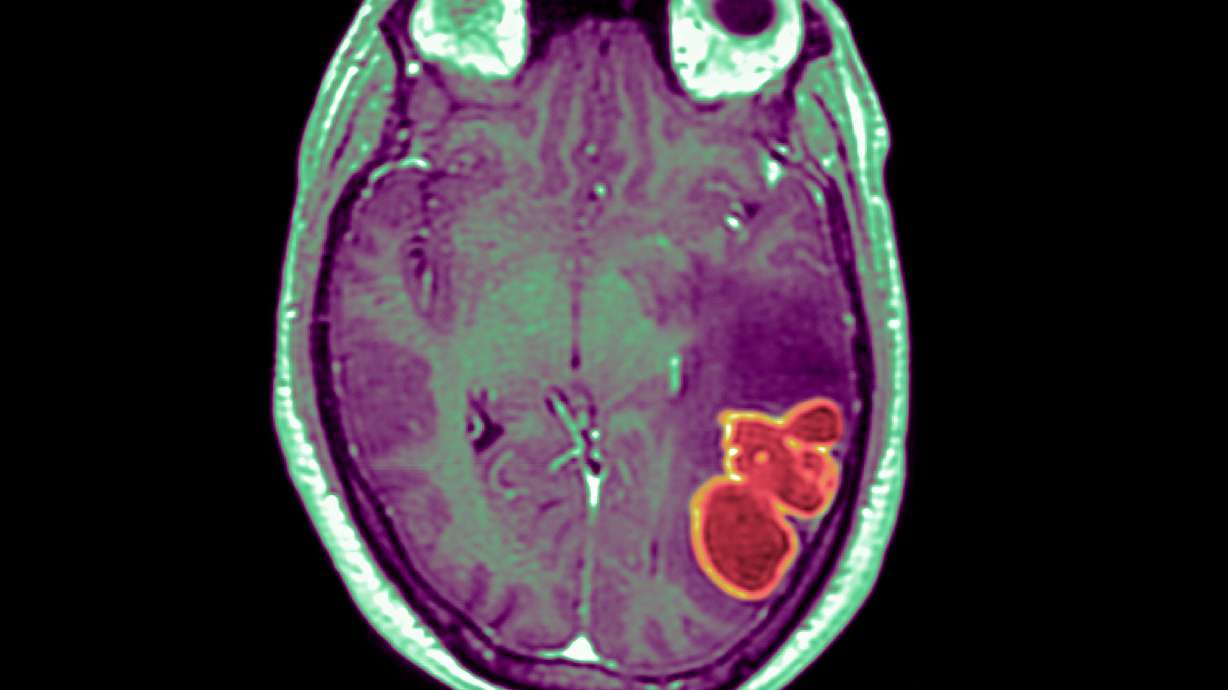

Cases of brain abscesses in American children have surged to new heights following the easing of pandemic restrictions, according to reports from the CDC. These abscesses, which are relatively rare but dangerous, are typically caused by bacteria or fungi entering the brain through respiratory infections such as COVID-19, the flu, or sinusitis. The CDC emphasizes the importance of children staying up-to-date with their vaccinations to prevent these infections. While cases have fallen since a peak in December 2022, they remain above the baseline maximum, indicating the need for continued monitoring and vigilance.